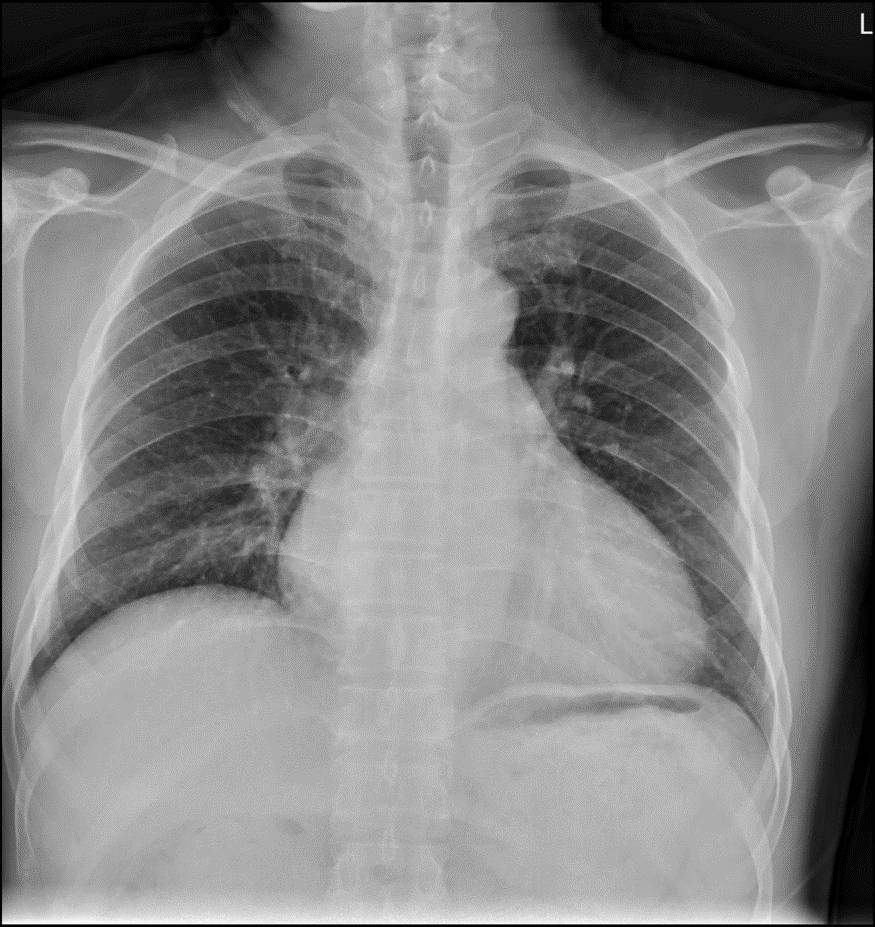

胸片

心脏扩大为突出表现,以左心室扩大主,伴以右心室扩大,也可有左心房及右心房扩大。